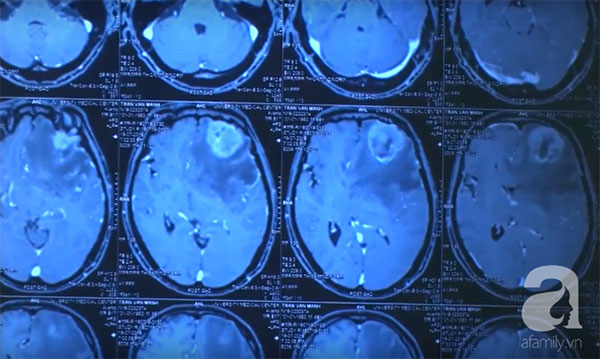

21/12/2018 15:45Cảnh báo: Ai hay ăn gỏi và rau sống, coi chừng bị ký sinh tấn công não nguy kịch như người đàn ông này

Đó là trường hợp của anh N.N.A. (52 tuổi, ngụ Lâm Đồng). Ít ngày trước, người đàn ông đến khám tại Bệnh viện Đại học Y Dược TPHCM (BV ĐHYD) với những triệu chứng đau đầu, yếu nửa người kèm co giật.

Thăm khám và thực hiện chụp cộng hưởng từ sọ não, các bác sĩ chẩn đoán bệnh nhân có tổn thương choáng chỗ vùng vỏ não vận động có thể do u hoặc nang kí sinh trùng trong não.

Tiến hành phẫu thuật, không nằm ngoài dự đoán ban đầu kíp mổ xác định bệnh lý của anh A. là u nang kí sinh trùng trong não.

Các bác sĩ khoa Ngoại Thần kinh đã tiến hành lấy kí sinh trùng dài khoảng 7cm trong não người bệnh.

Hậu phẫu, bệnh nhân được tiếp tục điều trị bằng thuốc kháng kí sinh trùng. Sau 4 tuần điều trị, anh A. đã không còn đau đầu, không còn co giật, sức cơ hồi phục và được xuất viện.

TS.BS Nguyễn Minh Anh, Trưởng Khoa Ngoại Thần kinh BV ĐHYD, người trực tiếp thực hiện phẫu thuật cho biết, kết quả giải phẫu bệnh cho thấy loại ký sinh trùng sống trong não anh A. có tên khoa học Spirometra erinaceieuropaei hay còn gọi là sán nhái.

Người dân có nguy cơ nhiễm ký sinh trùng này khi ăn thịt ếch, nhái, gà, vịt, chim không nấu chín kỹ. Sán nhái thường kí sinh ở mắt người, rất hiếm khi có ở não.

Trường hợp người bệnh này chỉ có 1 nang ký sinh trùng duy nhất. Nếu để tình trạng của kéo dài không điều trị, anh A. có nguy cơ nhiễm trùng, xuất huyết não, liệt nửa người không hồi phục và thậm chí tử vong" - Bác sĩ phân tích.